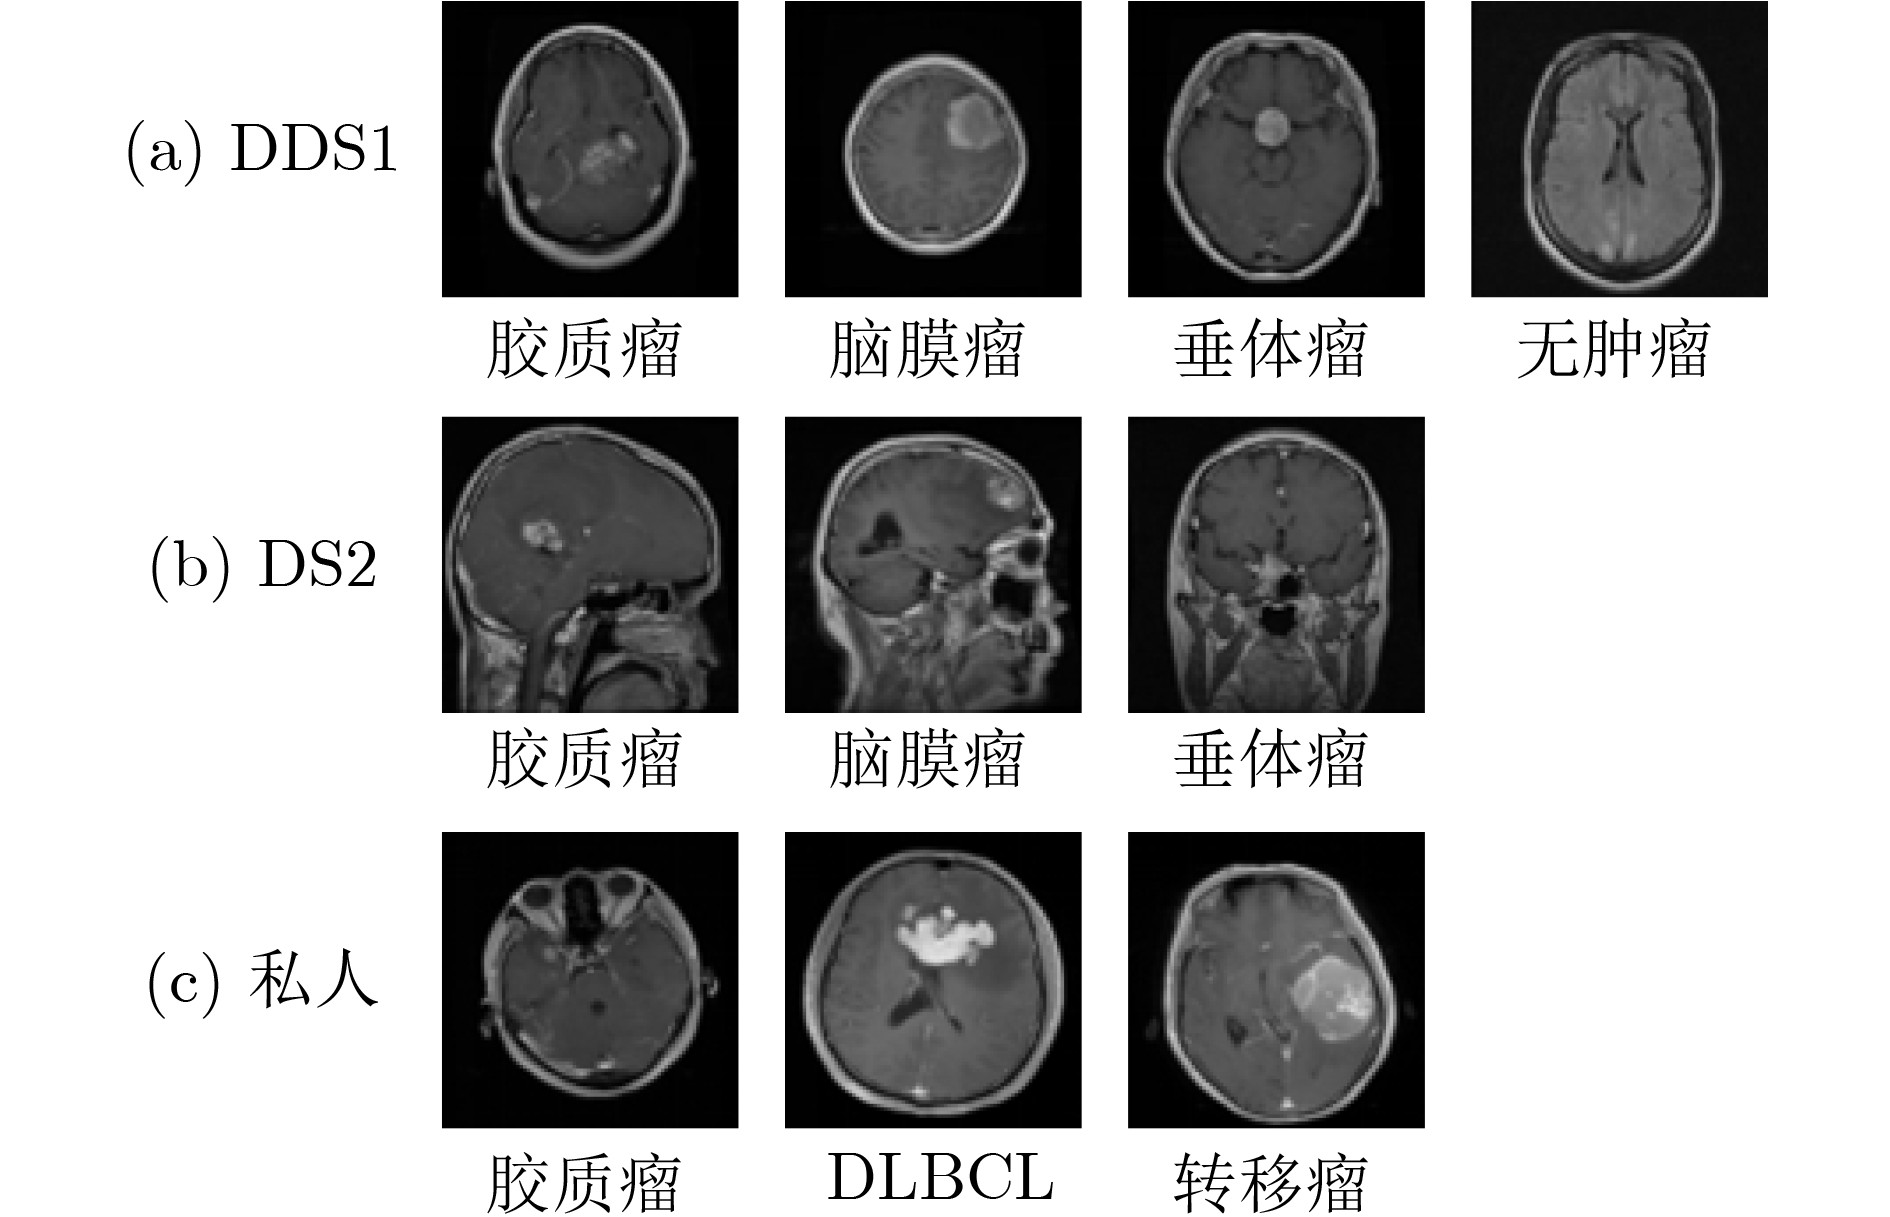

表 1 数据集信息

肿瘤类型 DS1 DS2 私人 脑膜瘤 1645 708 - 垂体瘤 1757 930 - 胶质瘤 1621 1426 891 DLBCL - - 468 转移瘤 - - 743 无肿瘤 2000 - - 总 数 7023 3064 2102 训练集 5712 2451 1680 测试集 1311 613 422 表 2 不同模型的测试集结果比较(%)